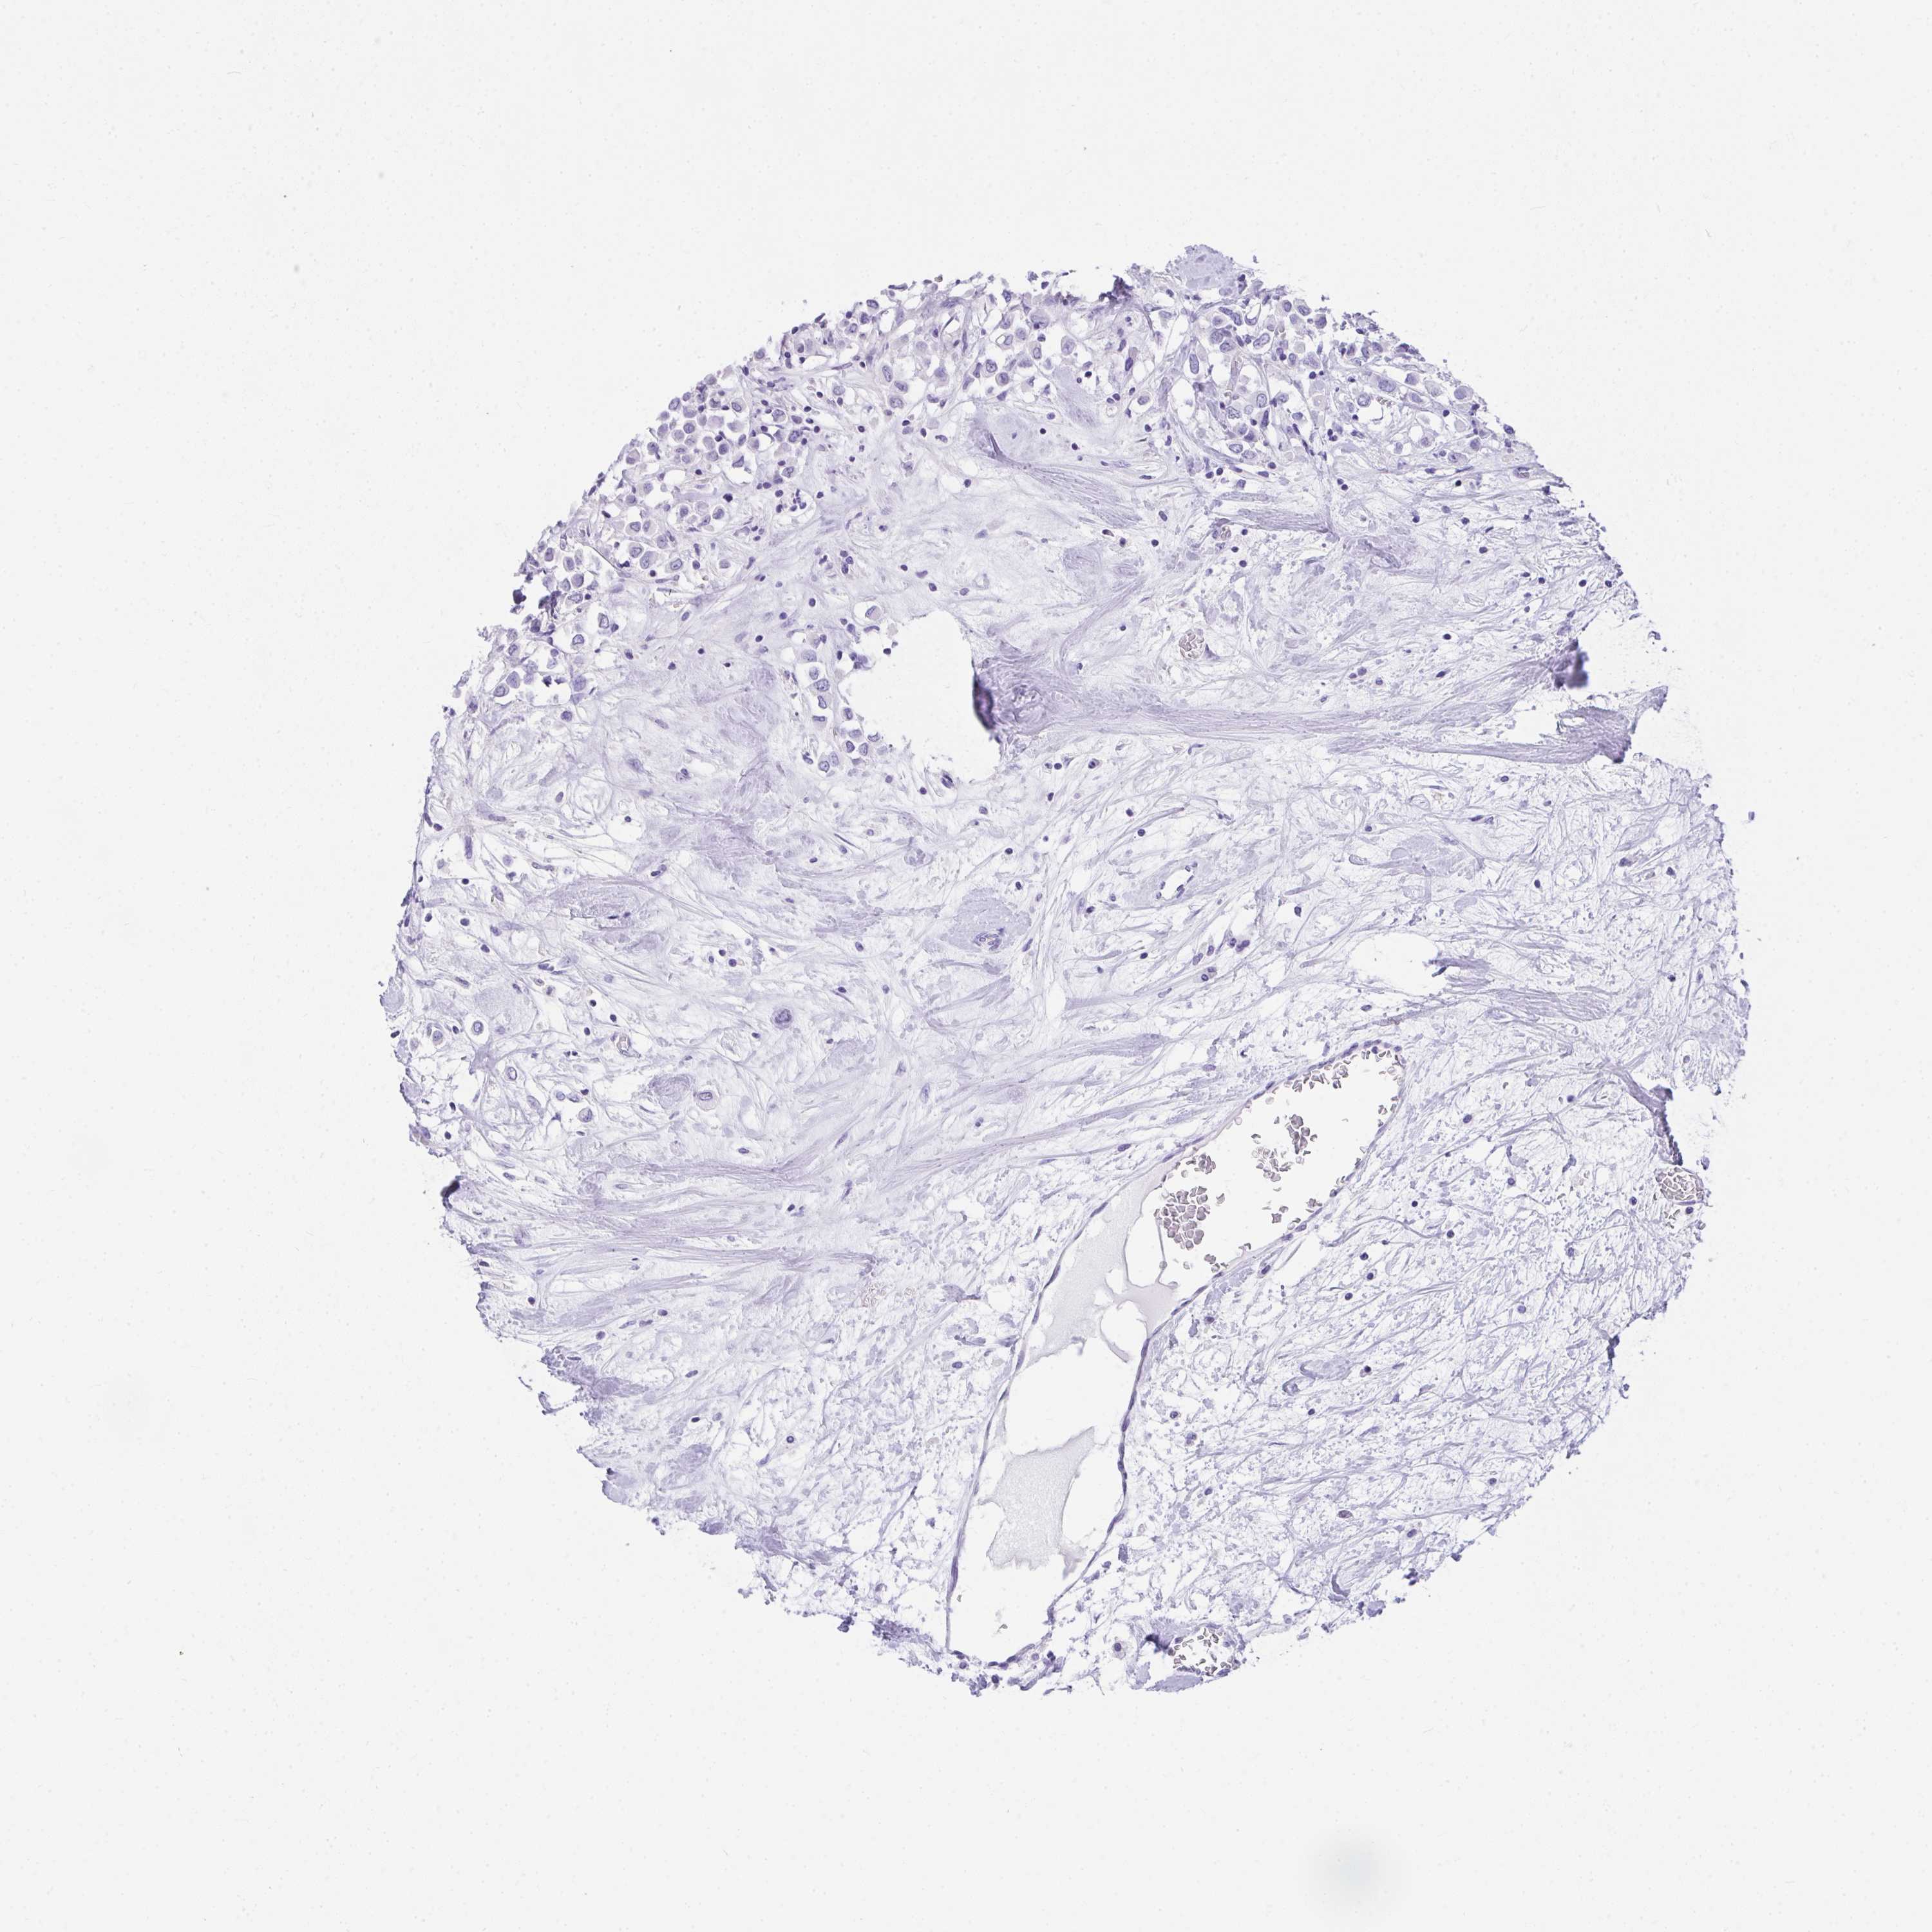

Breast cancer

Human cancer